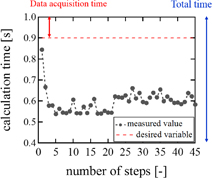

Examples of real-time LMI images are shown in Fig. 10. Maps of tissue displacement and normalized displacement are shown in Figs. 10(a) and 10(b), respectively. In this case, on-line LMI images were updated before the start of the next data acquisition. Simultaneously, the times for calculation including data transfer and displaying LMI were measured in each step; the results are shown in Fig. 11. The average and maximum calculation times were approximately 600 and 850 ms, respectively.

Standard image High-resolution imageFig. 11. Calculation time of real-time LMI for each step.

Download figure:

Using the real-time LMI system, on-line LMI images were updated every 1 s. When the coagulation size was 10 mm, the coagulation area expands at approximately 0.2 mm/s. Therefore, the temporal resolution of this system is sufficient to control coagulation size. Furthermore, oscillation data in 2 periods were acquired and analyzed in these experiments. To improve the speed of processing, only 1 period of oscillation data was used; in this case, the noise negatively effects the LMI images. When acquired data numbers are equal to an integral multiple (N times) of 1 period, the signal-to-noise ratio (SNR) is calculated:

times. Because the oscillation data were reduced to 1 period from 2 periods, SNR is  times. LMI images are not significantly affected by noise. There is a trade-off between temporal and spatial resolutions. In this case, temporal resolution is more important for the feedback control system. However, it is necessary that the data processing system be improved by use of a graphical processing unit (GPU) to improve both temporal and spatial resolutions.

The current computation time for LMI is about 0.9 s and the frame rate of LMI was 1 frame/s. Typical acquisition time of MRI thermometry is a few second. In this aspect, the imaging speed of LMI was not high. However, the data acquisition time for LMI was less than 10 ms for one data set. Therefore, LMI has the potential to be more than 100 times faster in its frame rate in principle. The signal process was calculated by Matlab code in a single CPU system. If the combination of a GPU for parallel processing and C code were to be used, this estimation of speed-up can be thoroughly realized. The current ratio of the rest time to the imaging period was only 17%. Therefore, if the time interval of between two 28-frame acquisitions is shorten, the efficiency of vibration and treatment is almost unchanged.